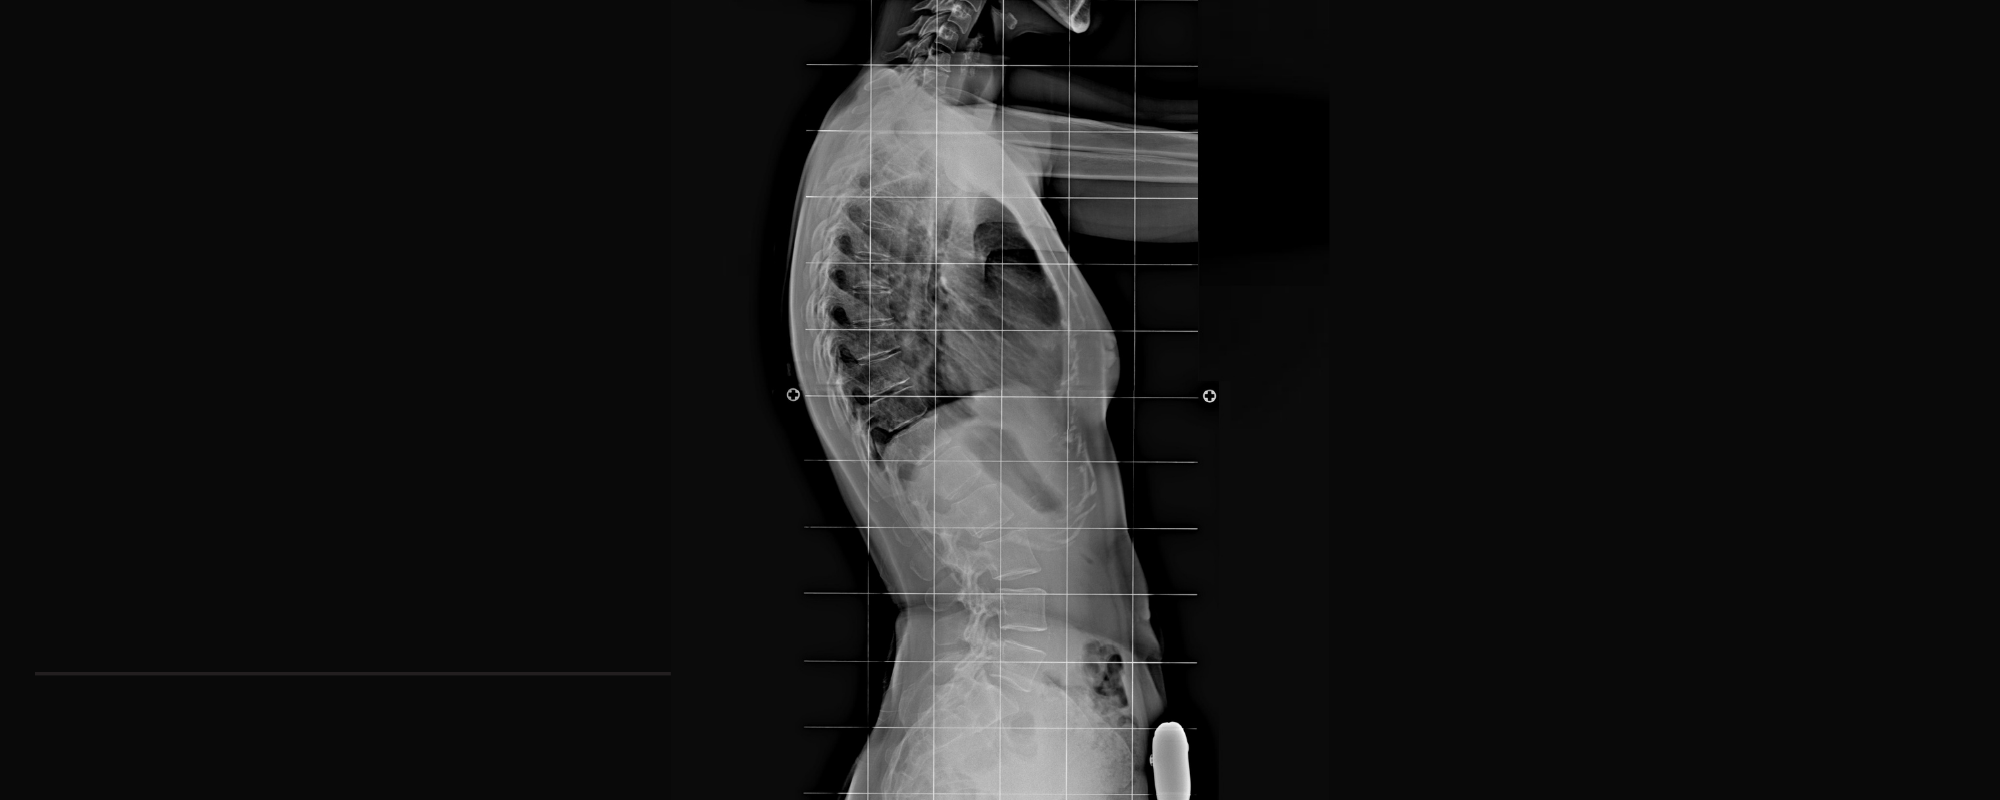

Lordoz Nedir? Lordoz Neden Olur?